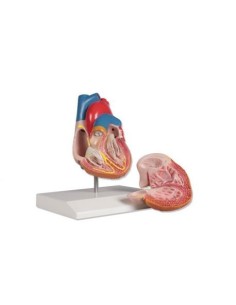

Dal cranio in 22 parti con incastri magnetici ai modelli di colonna vertebrale, da quelli di articolazioni a quelli di cuore, ogni pezzo della nostra collezione è progettato per un’immersione totale nello studio dell’anatomia umana. I nostri modelli, realizzati tramite scansioni di ossa vere, garantiscono un’esperienza tattile autentica e una fedeltà di peso quasi identica agli originali.

Essenziali per studenti e professionisti, i nostri modelli anatomici sono strumenti didattici che permettono di osservare le strutture anatomiche con precisione, eliminando la necessità di dissezioni o studi invasivi. Sono inoltre utili per spiegare ai pazienti le patologie, rendendo la comunicazione più efficace e risparmiando tempo prezioso.